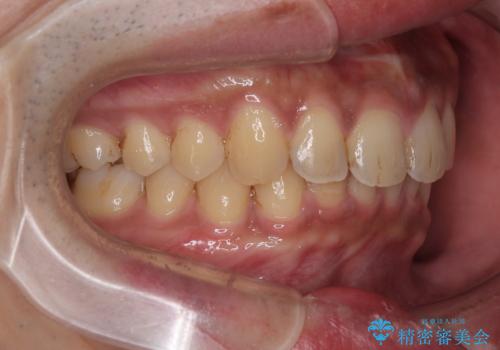

- 上の前歯の正中離開(すきっ歯)と、下顎前歯部の叢生(デコボコ)を主訴に来院された患者様の症例です。

「目立ちにくい装置で治療したい」とのご希望があり、透明のマウスピース矯正であるインビザラインを用いて矯正治療を行いました。